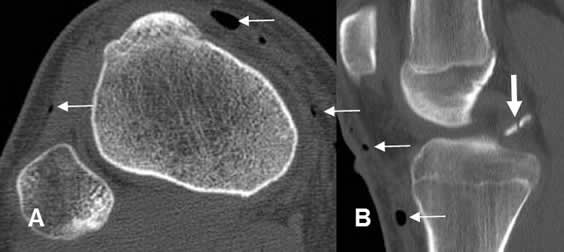

A: Rx lateral: Fractura conminuta e impactada del calcáneo.

B: TAC axial y C: TAC reconstrucción 3D: Múltiples fragmentos óseos, por estallido del calcaneo.